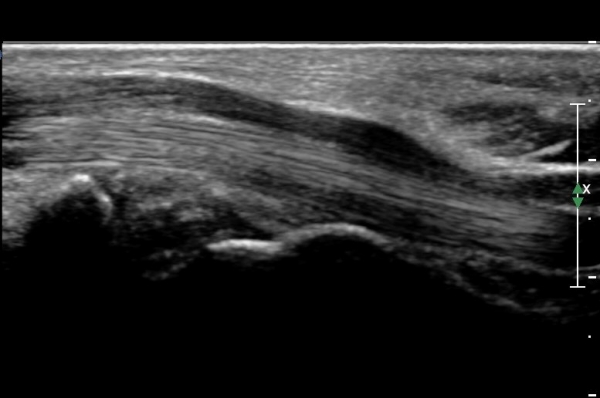

¼ö±Ù°ü ±ÙÀ§ºÎ(scaphoid, lunate level)¿¡¼­ Á¤Á߽Űæ Ⱦ´Ü¸é°Ë»ç»ó Á¤Á߽ŰæÀÇ Àú¿¡ÄÚ ºÎÁ¾ÀÌ °üÂûµÊ.(»çÁø 2).